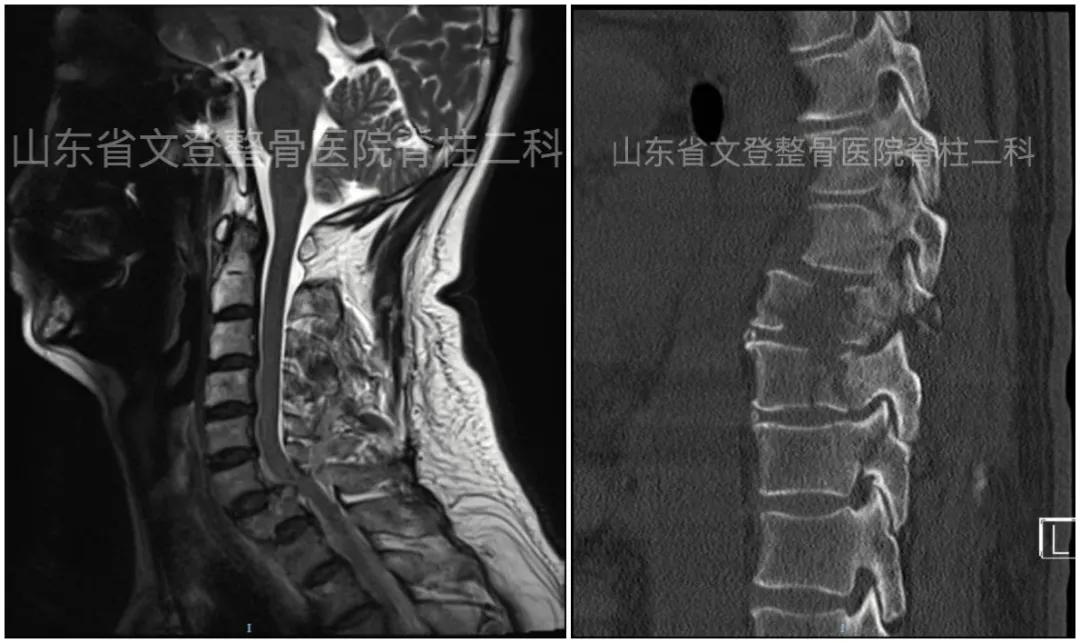

术前颈椎MRI(矢状位) 术前胸椎CT(矢状位)

姜传杰主任查看病人认为病情复杂,目前患者面临两个主要问题:一是胸部损伤,二是下肢静脉血栓栓塞。两个原因均可能导致严重并发症,甚至病人死亡,应及时处理。针对患者胸部损伤且多发性肋骨骨折,外科彭志清主任进行了会诊并转入外科行胸腔闭式引流。邹娟主治医师结合CT及时抽取胸腔积液及积气,快速有效的控制了病情。

胸腔积液处理前、后